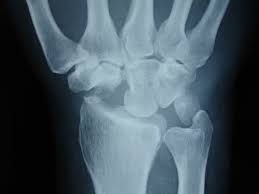

1 2 3 4 5 6. Hier ist die Radiusfraktur nicht mit einer Platte sondern mit Kirschnerdrähten erfolgt. Wenn nun diese Schrauben entfernt werden kann es passieren dass die Knochen dann keinen Halt mehr haben und auseinander oder zusammen fallen.

Gelegentlich ist es nicht möglich das Material vollständig zu entfernen so dass es auch vorkommen kann dass Reste des Metalls im Körper belassen werden müssen. Ich habe neulich das Gleiche bei einem Schrank erlebt. Die Stabilität sollte nach der Entfernung kein Problem sein weil die Schrauben und Nägel immer versetzt angeordet sind also die Löcher nie über- untereinander lägen. Die ist hart und sehr spitz und lässt sich nicht bewegen. Sollten Metallteile weggebrochen sein werden die dann auch im Knochen belassen die tun nix. Hier ist die Radiusfraktur nicht mit einer Platte sondern mit Kirschnerdrähten erfolgt. Obwohl ein Schraubenloch noch lange im Röntgenbild nachweisbar ist kommt es zu einer fortschreitenden Geflechtknochenbildung die die Stresskonzentration im Schraubenloch zunehmend herabsetzt. Hierbei wird in manchen Fällen lediglich die einzelne Stellschraube entfernt wobei die komplette Metallentfernung ungefähr nach einem Jahr beginnt. Auch nach einem Jahr kann man im Röntgenbild nach einer Schraubenentfernung die Schraubenkanäle gut erkennen.